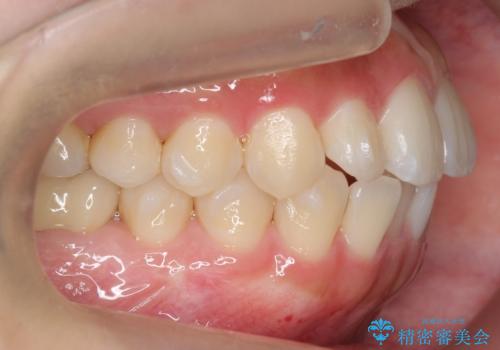

インビザライン モニターで前歯をきれいに

- 前歯のがたつきをきにされていました。

上下の前歯をやすりがけする処置(IPR)を行い、前歯の並びを出っ歯にしないようにしながら整えました。

症状が軽度であるためモニター採用になりました。